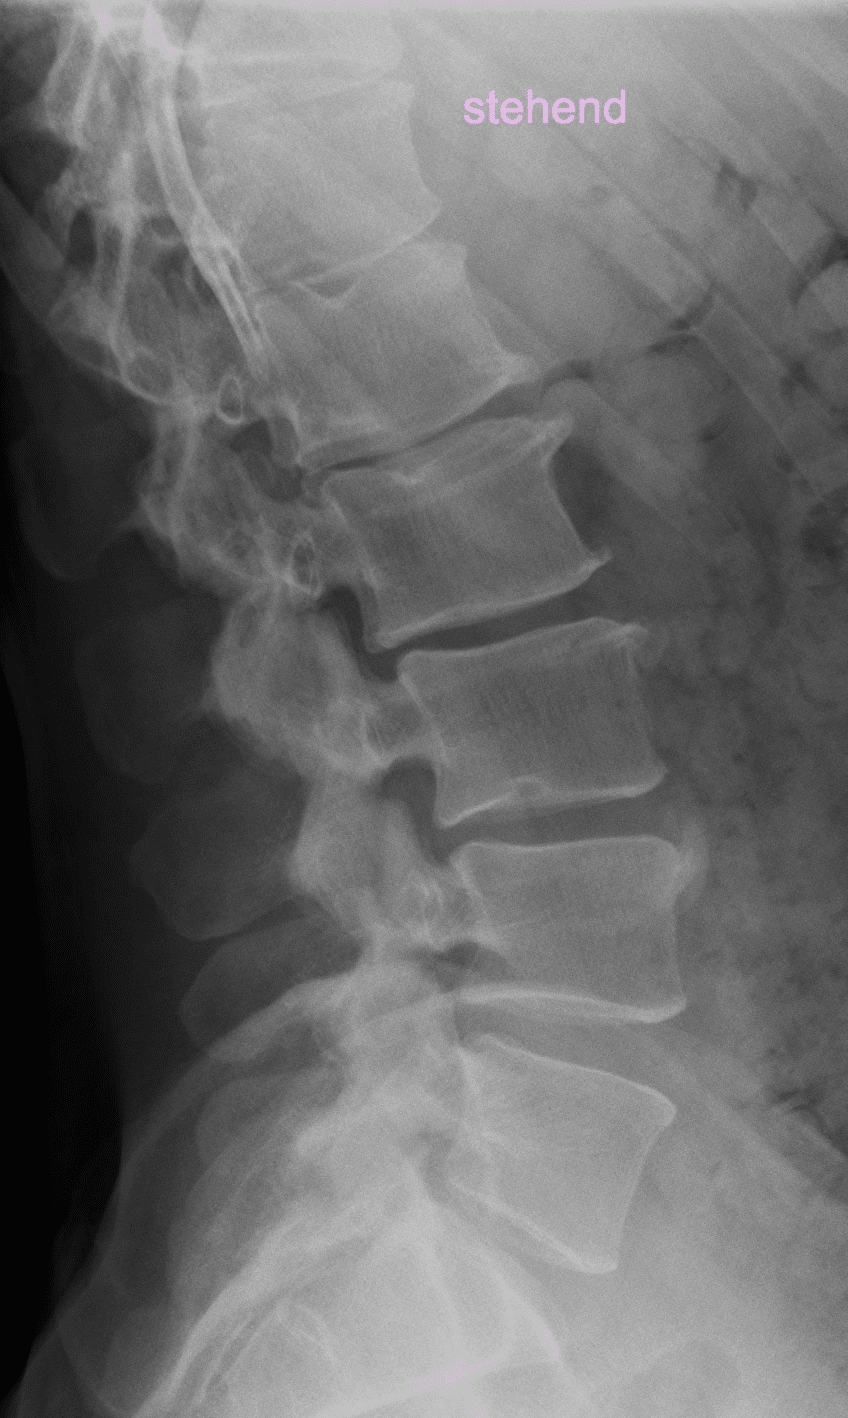

Rückenschmerzen zählen zu den häufigsten orthopädischen Beschwerden überhaupt. Hinter dem Begriff verbirgt sich eine Vielzahl an möglichen Ursachen, die erst durch die richtige Kombination aus klinischer Untersuchung, bildgebender Diagnostik und dem Beobachten des zeitlichen Verlaufs zuverlässig identifiziert werden können. Ziel der orthopädischen Abklärung ist es, unspezifische Rückenschmerzen von spezifischen, klar anatomisch bedingten Ursachen zu unterscheiden. Nur so lässt sich eine wirksame und langfristig erfolgreiche Therapie festlegen.

Rückenschmerzen können durch funktionelle Fehlbelastungen, muskuläre Dysbalancen oder anatomische Veränderungen entstehen. Zu den spezifischen Ursachen zählen:

- Facettengelenk-Syndrom: Reizung oder Arthrose kleiner Wirbelgelenke

- Bandscheibenvorfall: Verlagerung von Bindegewebe an die Nervenwurzel mit entsprechenden Funktionsausfällen und Schmerzen

- Aktivierte Osteochondrose: Entzündliche Reaktionen bei degenerativen Bandscheibenveränderungen

- Osteoporotische Wirbelkörpersinterung oder -fraktur: Schmerz durch Wirbelkörpereinbruch

- Wirbelgleiten (Spondylolyse/Spondylolisthese): Instabilität der Wirbelsäule